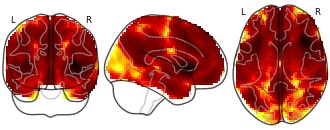

Detailed information of the between-condition differences in the PCC-FC maps...

EmailClick to copy linkLink copied CiteChaogan Yan; Dongqiang Liu; Yong He; Qihong Zou; Chaozhe Zhu; Xinian Zuo; Xiangyu Long; Yufeng Zang (2023). Detailed information of the between-condition differences in the PCC-FC maps within the DMN. [Dataset]. http://doi.org/10.1371/journal.pone.0005743.t001xlsAvailable download formatsUnique identifierhttps://doi.org/10.1371/journal.pone.0005743.t001Dataset updatedJun 4, 2023Dataset provided byPLOS ONEAuthorsChaogan Yan; Dongqiang Liu; Yong He; Qihong Zou; Chaozhe Zhu; Xinian Zuo; Xiangyu Long; Yufeng ZangLicense

CiteChaogan Yan; Dongqiang Liu; Yong He; Qihong Zou; Chaozhe Zhu; Xinian Zuo; Xiangyu Long; Yufeng Zang (2023). Detailed information of the between-condition differences in the PCC-FC maps within the DMN. [Dataset]. http://doi.org/10.1371/journal.pone.0005743.t001xlsAvailable download formatsUnique identifierhttps://doi.org/10.1371/journal.pone.0005743.t001Dataset updatedJun 4, 2023Dataset provided byPLOS ONEAuthorsChaogan Yan; Dongqiang Liu; Yong He; Qihong Zou; Chaozhe Zhu; Xinian Zuo; Xiangyu Long; Yufeng ZangLicenseAttribution 4.0 (CC BY 4.0)https://creativecommons.org/licenses/by/4.0/

License information was derived automaticallyDescriptionThe statistical threshold was set at |t|>2.093 (P486 mm3, which corresponds to a corrected P

TwitterDetailed information of the between-condition differences in the PCC-FC maps within the DMN.

The statistical threshold was set at |t|>2.093 (P486 mm3, which corresponds to a corrected P